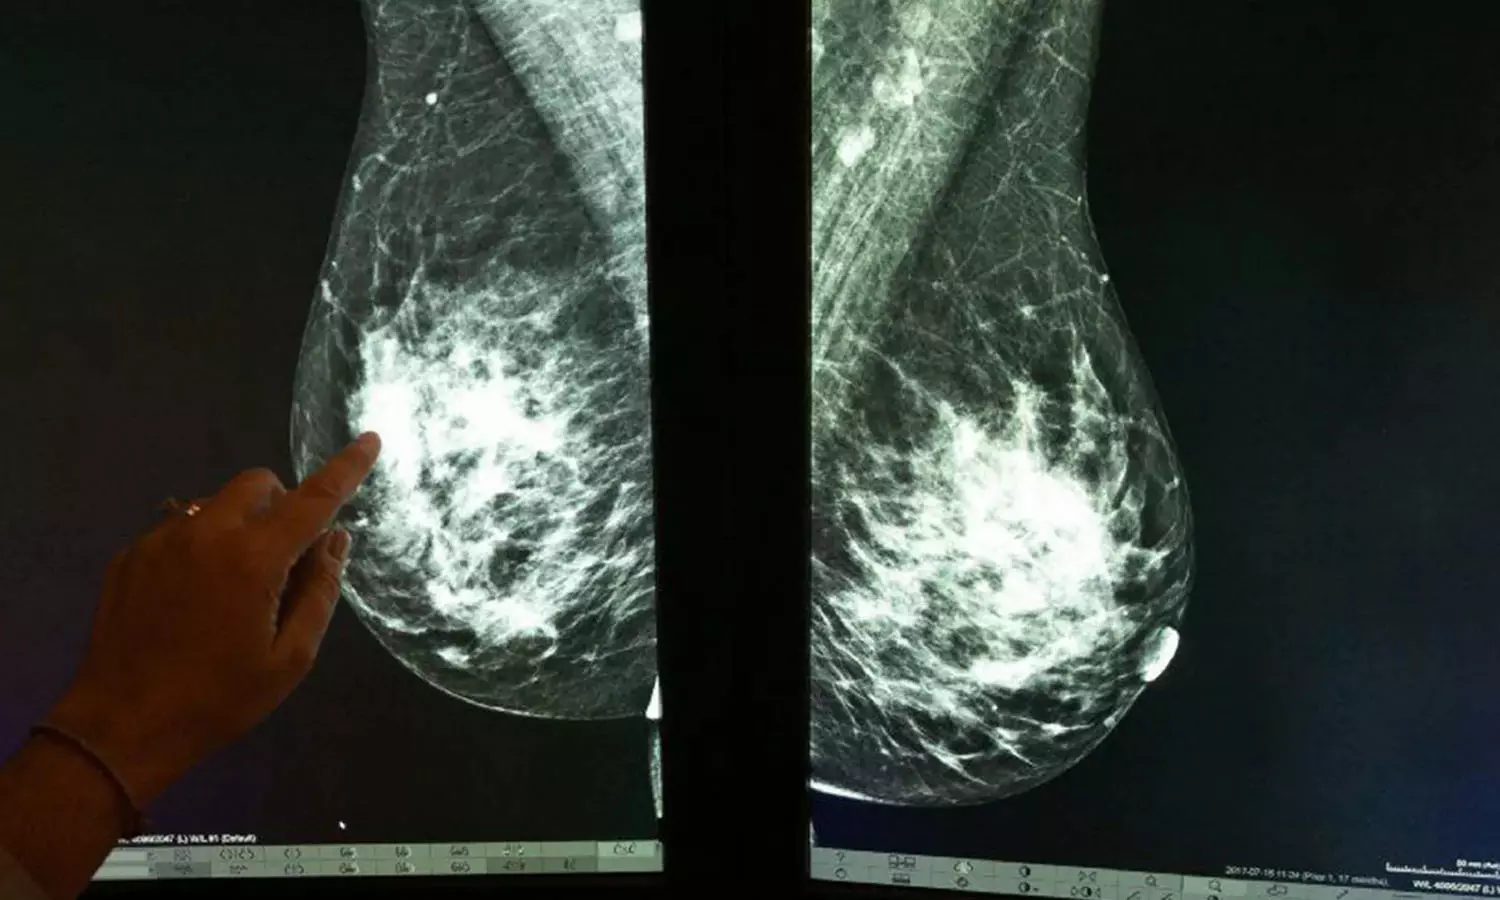

മറ്റേതു രോഗത്തെയും പോലെ തുടക്കത്തിൽ തിരിച്ചറിഞ്ഞാൽ സുഖപ്രദമാക്കാവുന്ന രോഗമാണ് അർബുദം. എല്ലാ തരം കാൻസറുകളും ആരംഭ ദിശയിൽ അറിഞ്ഞെന്നു വരില്ല. എന്നാൽ സ്വയം പരിശോധനയിലൂടെ തുടക്കത്തിലേ കണ്ടുപിടിച്ചാൽ 100 ശതമാനവും ചികിത്സിച്ച് ഭേതമാക്കാൻ കഴിയുമെന്നത് സ്തനാർബുദത്തെ മറ്റർബുദങ്ങളില് നിന്നും വ്യത്യസ്തമാക്കുന്നു.

സ്തനങ്ങളിൽ വരുന്ന വലിപ്പ വ്യത്യാസം, സ്തനങ്ങളിൽ രൂപപ്പെടുന്ന മുഴ, കക്ഷ ഭാഗത്തെ മുഴകൾ, സതനങ്ങളിലെ നിറവ്യത്യാസം, മുലകണ്ണില് നിന്ന് പുറത്തേക്ക് വരുന്ന സ്രവം തുടങ്ങിയവ കൃത്യമായും നിരീക്ഷിക്കേണ്ടതുണ്ട്. ഇത് അർബുദം കാരണമല്ലെന്ന് ഉറപ്പു വരുത്തണം. മാറിടങ്ങള് കൈകൊണ്ട് പരിശോധിക്കുന്നതിലൂടെ ശരീരത്തിലെ മുഴകൾ കണ്ടെത്താൻ കഴിയും.

സ്റ്റേജ് ഒന്നിലോ രണ്ടിലോ ആണ് കണ്ടുപിടിക്കുന്നതെങ്കിൽ കൃത്യമായ ചികിത്സയിലൂടെ കാൻസർ ഭേതമാക്കാം. എന്നാൽ നാലോ അഞ്ചോ സ്റ്റേജാണ് എങ്കിൽ ഇത്തരക്കാരിൽ ശസ്ത്രക്രിയയോടൊപ്പം കീമോ തെറാപ്പിയും റേഡിയേഷൻ ചികിത്സയും മറ്റു ചികിത്സകളും ആവശ്യമായി വരുന്നു.